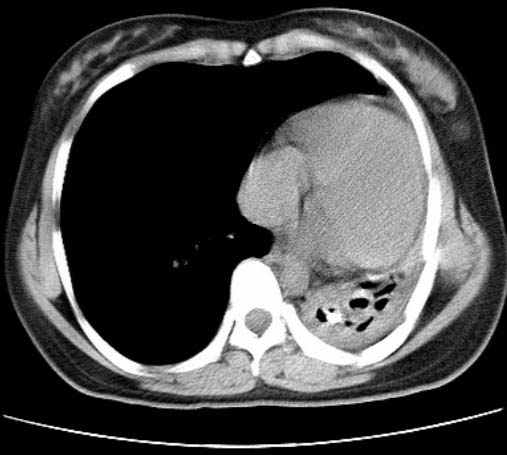

标题: CT25648:求教:是肺发育不全还是结核?

女  20岁。一月前咳血,诊“肺结核”抗痨治疗一月后,咳血停止,现复查。病人精神好。前后ct片对比未见明显变化。既往体检“正常”

1)考虑左肺结核并肺不张、支气管扩张。2)纵隔疝。

考虑左肺结核,左肺毁损,纵膈左偏,既往体检正常不可靠,tb一个月也不会这个样子的,有钙化,应该病程较长,冰冻三尺非一日之寒!

左肺发育不全。

结核,左肺毁损。